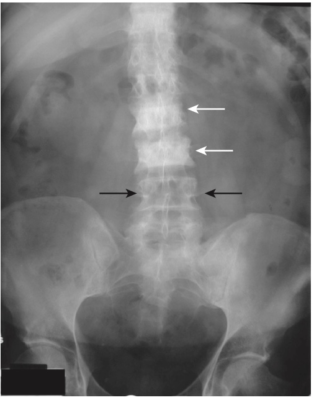

- Một chất được tiết từ các tế bào u của ung thư biểu mô tuyến tiền liệt có thể kích thích hoạt động của tạo cốt bào và tạo ra các vùng tăng đậm độ xương khu trú. Những tổn thương này thường thấy nhất ở đốt sống, xương sườn, xương chậu, xương đùi và xương đùi (Hình-5).